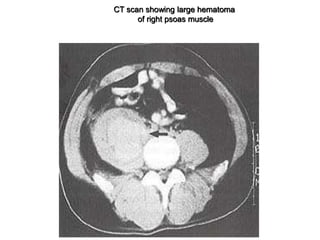

CT scan showing large hematoma

of right psoas muscle

Coagulation factor disorders